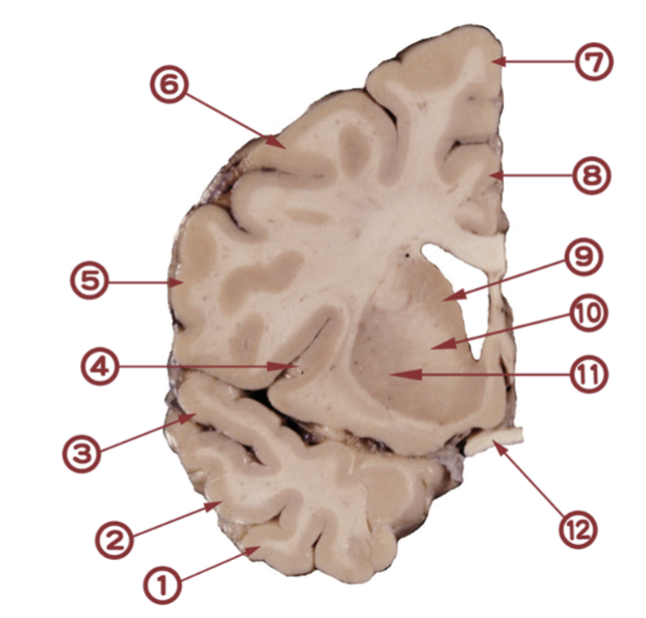

Den här är lite svårare, det är korrekt. Titta och klura, vilken siffra markerar nucleus lentiformis? (1p)